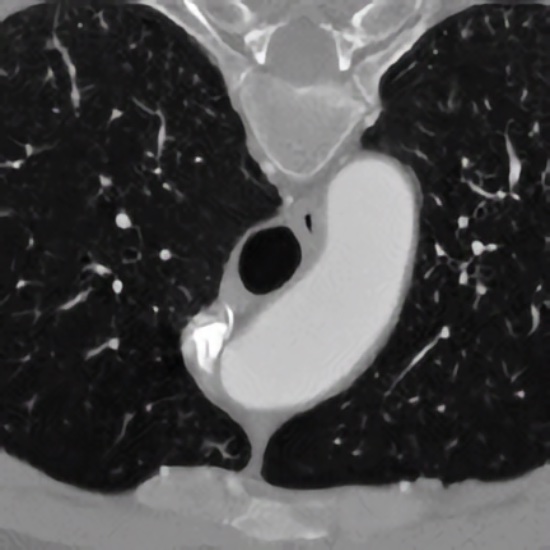

Development of model-based approaches for accurate quantification of the 3D morphology of human blood vessels from 3D tomographic images (e.g., 3D CTA, 3D MRA). The approaches combine 3D cylindrical intensity models with incremental model fitting. The main application domain is the quantification of the aortic arch and its main bifurcating branches for improved operation planning using stent grafts.

3D Quantification of the Aortic Arch Morphology in 3D CTA Data for Endovascular Aortic Repair

Wörz S, von Tengg-Kobligk H, Henninger V, Rengier F, Schumacher H, Böckler D, Kauczor HU, and Rohr K

IEEE Transactions on Biomedical Engineering

Combined Model-Based Segmentation and Elastic Registration for Accurate Quantification of the Aortic Arch

Biesdorf A, Rohr K, von Tengg-Kobligk H, and Wörz S

Model-Based Segmentation and Motion Analysis of the Thoracic Aorta from 4D ECG-Gated CTA Images

Biesdorf A, Wörz S, Müller T, Weber TF, Heye T, Hosch W, von Tengg-Kobligk H, and Rohr K

Proc. 14th Internat. Conf. on Medical Image Computing and Computer-Assisted Intervention (MICCAI'2011)